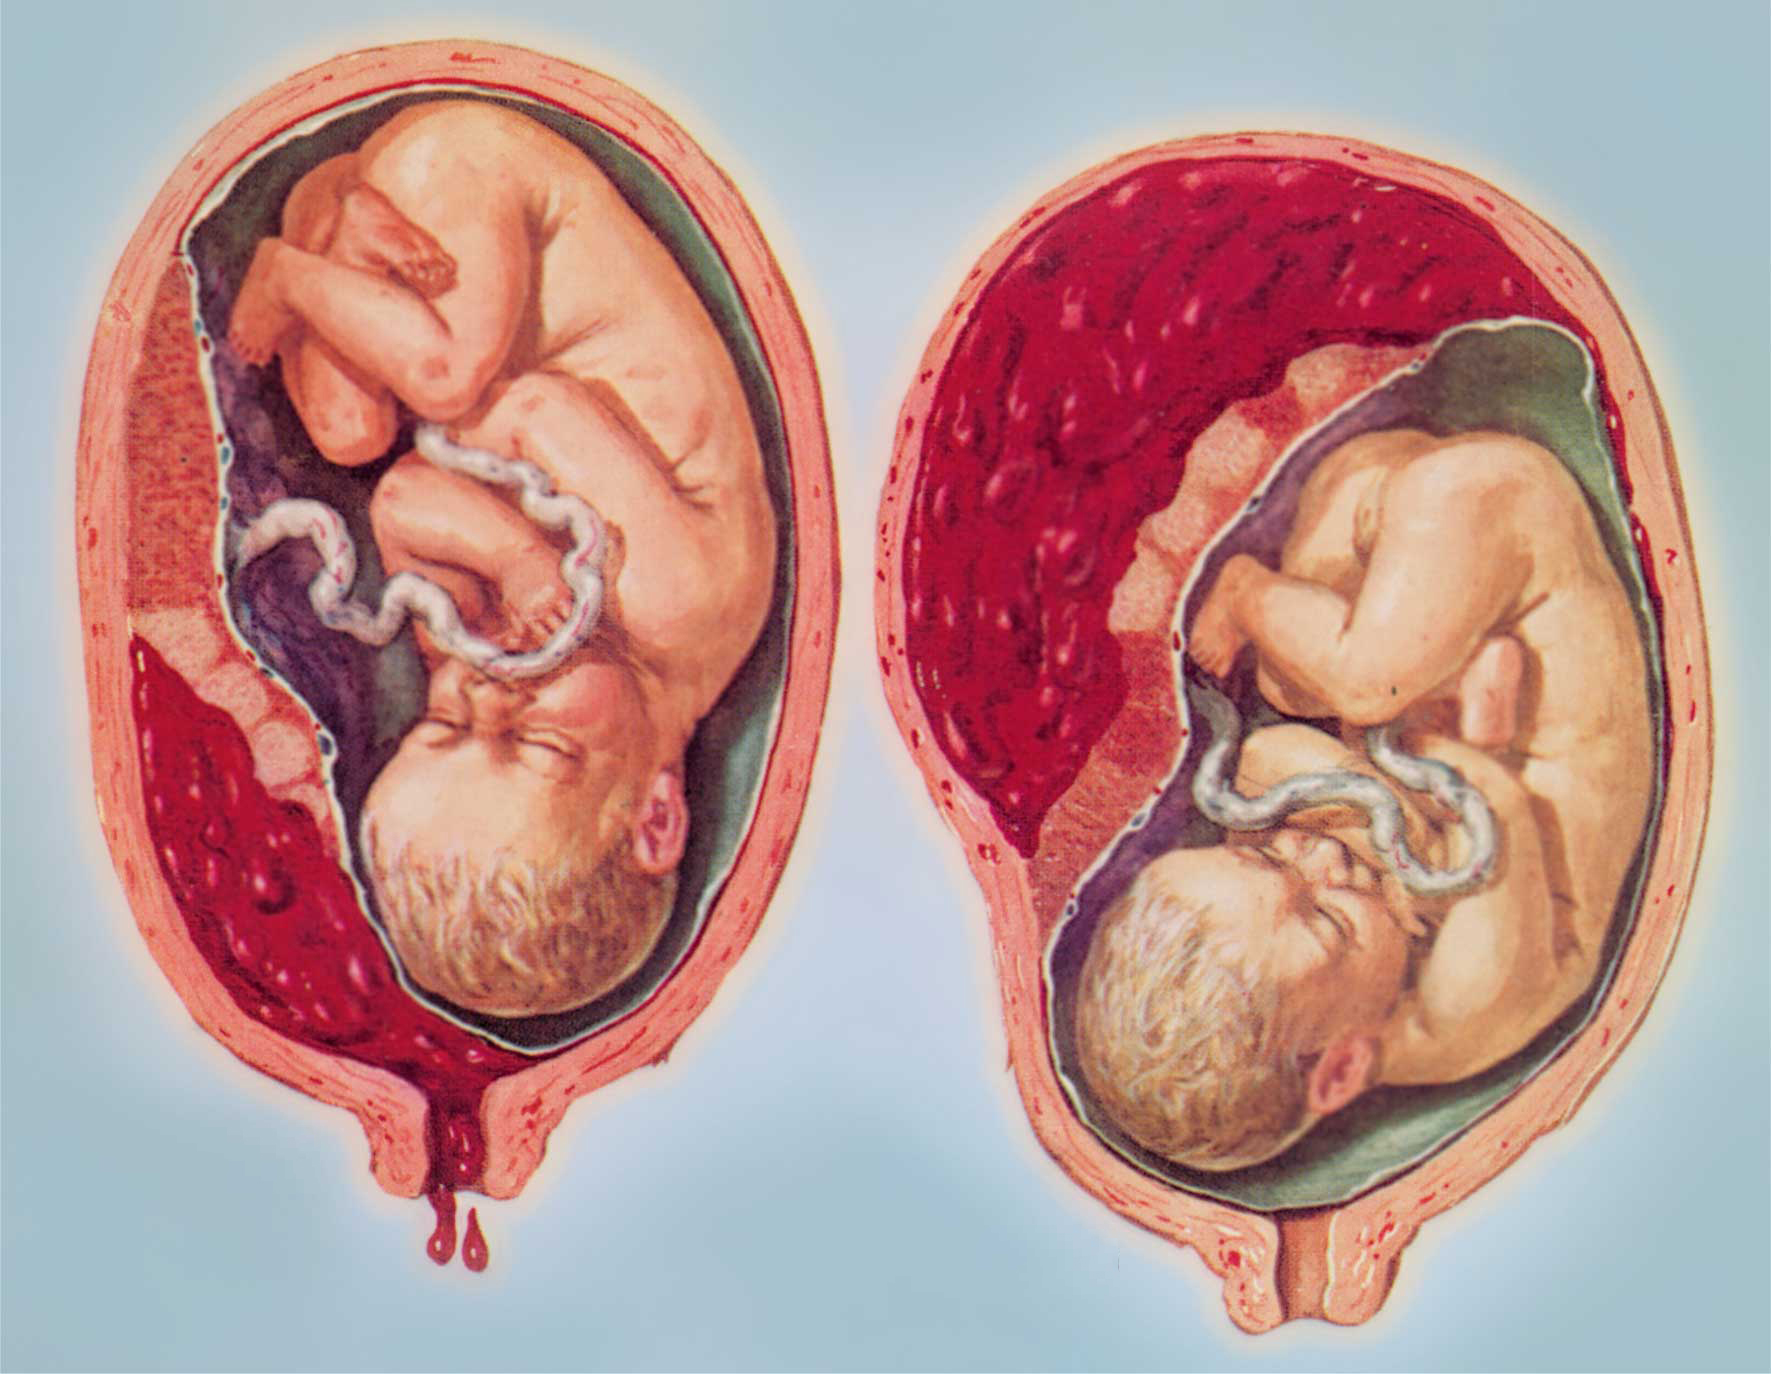

Околоплодный пузырь и плацента: структура и функции